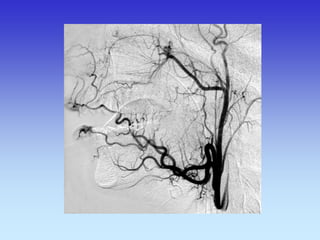

METODE PRIKAZA KRVNIH ŽILA

•UZ-DOPPLER

•DSA

•CTA

•MRA

A-V MALFORMACIJA